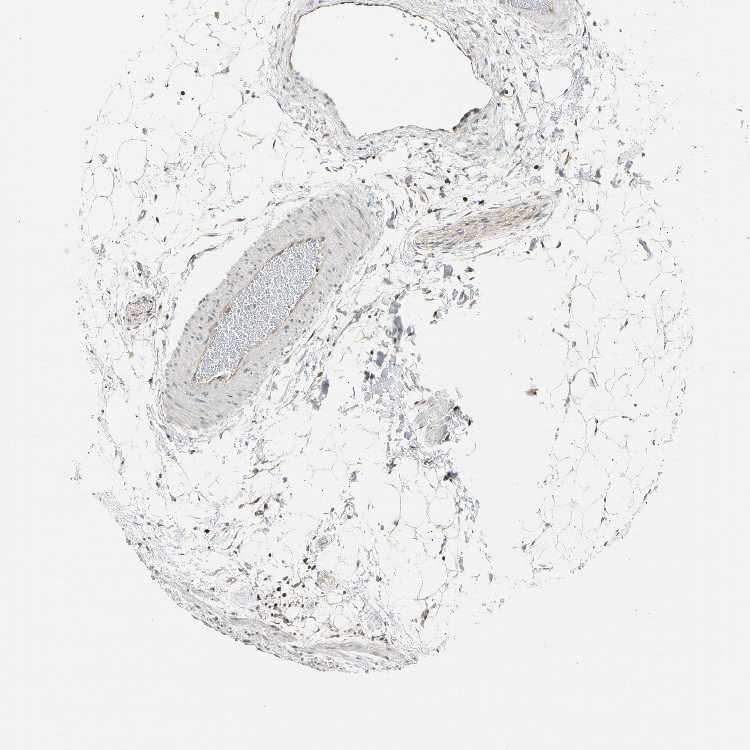

SOFT TISSUE 1 - Antibody stainingi

Antibody staining in the annotated cell types in the current human tissue is reported as not detected, low, medium, or high, based on conventional immunohistochemistry profiling in selected tissues. This score is based on the combination of the staining intensity and fraction of stained cells.

Each image is clickable and will lead to virtual microscopy that enables deeper exploration of all samples and also displays staining intensity scores, fraction scores and subcellular localization as well as patient and tissue information for each sample.

Antibody HPA007890Antibody HPA013355

Chondrocytes Low-

Fibroblasts LowNot detected

Peripheral nerve Not detectedMedium

SOFT TISSUE 2 - Antibody stainingi

Fibroblasts Not detectedHigh

Peripheral nerve MediumMedium